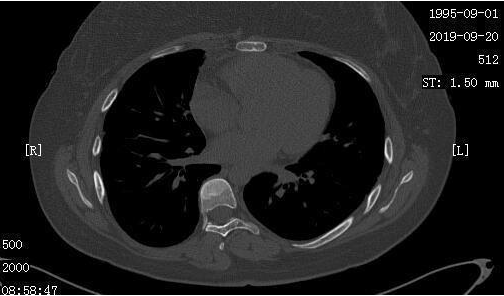

小周和她的家人非常高兴,同时也更加积极的配合医生进行治疗,加上小周平时也按时、适量的锻炼,逐渐的,小周发现自己的食欲也好起来了,抵抗力也增强了,到9月份再次复查的时候,我们发现小周的肺部情况非常好,同时全身骨转移灶也减少了。

2019-9-20日CT

2019-9-20日CT骨窗:骨转移灶减少